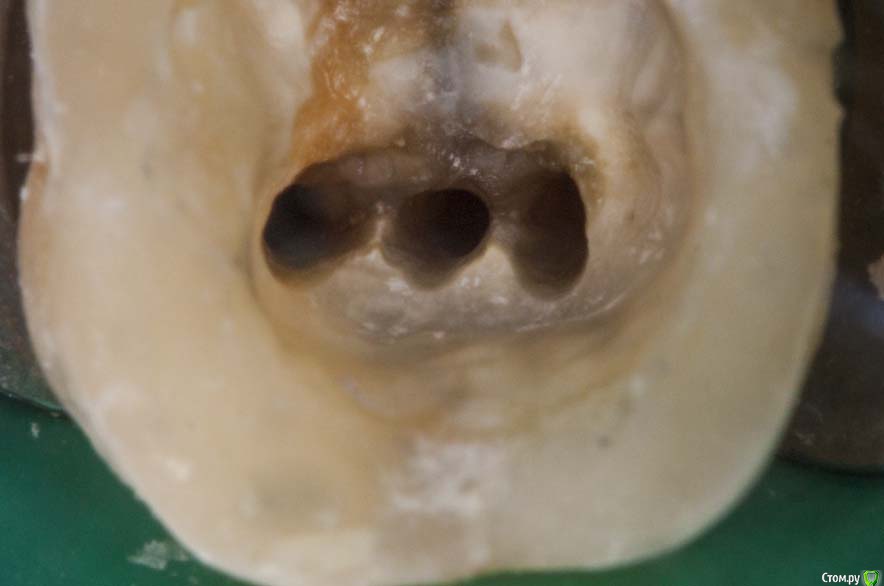

M@estro Опубликовано 27 января, 2016 Автор Поделиться Опубликовано 27 января, 2016 Повторное эндо ( ре-колл 7 месяцев) . 5 каналов в 3.6 . Обтурация - CWCT . Мех.обработка - Profile + m2 . Ca(OH)2 на 2 недели 12 Ссылка на комментарий

M@estro Опубликовано 3 декабря, 2014 Автор Поделиться Опубликовано 3 декабря, 2014 Мне в увеличении хорошо видно, работала ли апикальная часть инструмента , и с какого размера она работала.По поводу всяких общих рекомендаций - сколько каналов в премоляре ? На "подумать" скину картинку : http://s020.radikal.ru/i704/1412/d1/2eaf7d816fea.jpg 2 Ссылка на комментарий

Гарриевич Опубликовано 19 декабря, 2014 Поделиться Опубликовано 19 декабря, 2014 Мне в увеличении хорошо видно, работала ли апикальная часть инструмента , и с какого размера она работала. По поводу всяких общих рекомендаций - сколько каналов в премоляре ? На "подумать" скину картинку : о-ф-и-г-е-т-ьмне в 3.3 нифига не видно) 1 Ссылка на комментарий